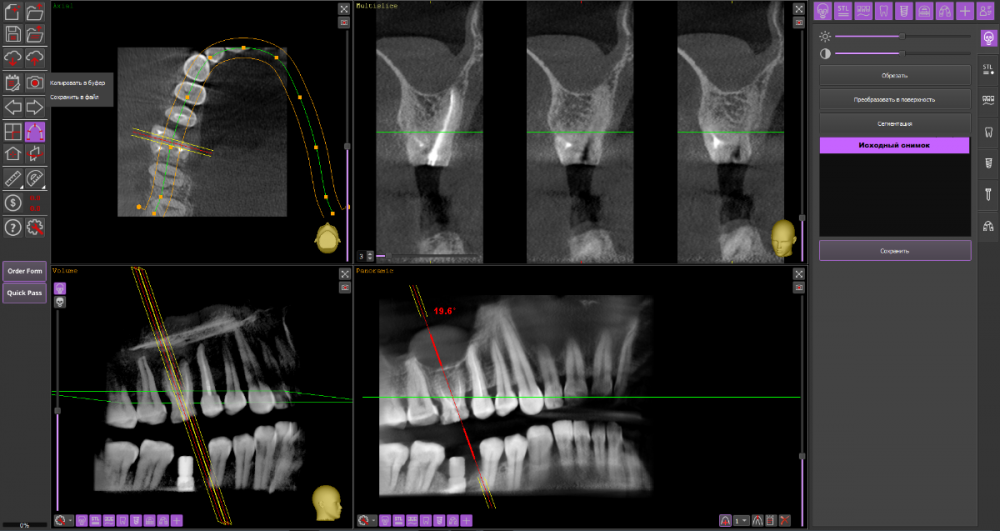

Алексей82 Опубликовано 10 марта, 2022 Автор Поделиться Опубликовано 10 марта, 2022 Здравствуйте. Вот ссылка на КТ. Посмотрите пожалуйста. Или может надо было скрин сделать чегото. https://dropmefiles.com/zxr3f Ссылка на комментарий

wladdX Опубликовано 10 марта, 2022 Поделиться Опубликовано 10 марта, 2022 (изменено) Попробовать поработать в корневых каналах можно, насколько это будет успешно, сказать невозможно. Изменено 10 марта, 2022 пользователем wladdX 1 1 Ссылка на комментарий